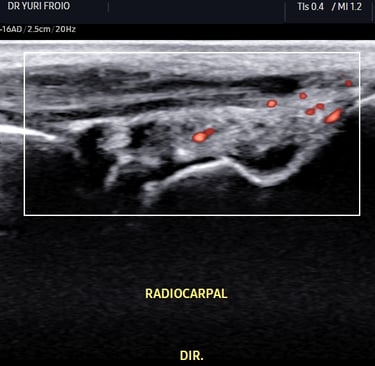

Ecografia Vascular com Doppler

A ecografia vascular com Doppler avalia o fluxo sanguíneo em artérias e veias identificando obstruções, varizes e tromboses. É um exame não invasivo, essencial para diagnóstico e acompanhamento de doenças vasculares. Proporciona informações detalhadas para uma abordagem clínica precisa.